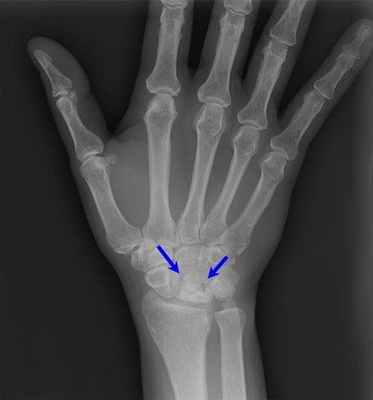

Большинство пациентов жалуются на боль запястье, усиливающуюся при нагрузке. При осмотре определяется болезненность в проекции полулунной кости. Первые шаги для диагностики болезни Кинбека — это сбор анамнеза, осмотр и рентгенограммы. Иногда требуются дополнительные исследования, наиболее информативным из которых является магнитно-резонансная томография. Именно МРТ позволяет выявить нарушение кровоснабжения полулунной кости, когда еще нет изменений на рентгенограммах. Также могут применяться компьютерная томография или остеосцинтиграфия.

В дальнейшем рентгенологически определяются, деформация полулунной кости, сплющивание вдоль продольной оси и укорочение в поперечнике. Контуры кости становятся неровными; в центре определяются участки просветления, которые соответствуют зонам рассасывания кости. Не часто, но отмечаются сужение суставной щели, как проявление деформирующего остеоартроза. Также могут определяться рентгенологические признаки ложного сустава полулунной кости, патологические переломы, полулунная кость может стать фрагментированной, т.е. распасться на части.

Рентгенограмма при болезни Кинбека.

МРТ и КТ являются наиболее чувствительными при диагностике болезни Кинбека; простая рентгенография показывают отклонения позже, как правило, при начале склеротических изменений полулунной кости, сменяющихся кистозными изменениями, фрагментацией и коллапсом.